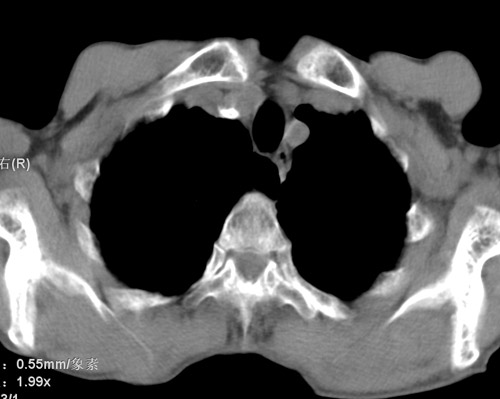

标题: CT17529:男 76 胸背部不适半月 胸透支气管炎 行CT检查 [打印本页]

标题: CT17529:男 76 胸背部不适半月 胸透支气管炎 行CT检查

意见 老年肺 少许炎症 肺大泡 右肺门略大 但支气管通畅  请各位高手指教如何下意见

间质纤维化伴少许炎症!另:肺大泡形成!

慢支肺气肿,肺动脉高压.